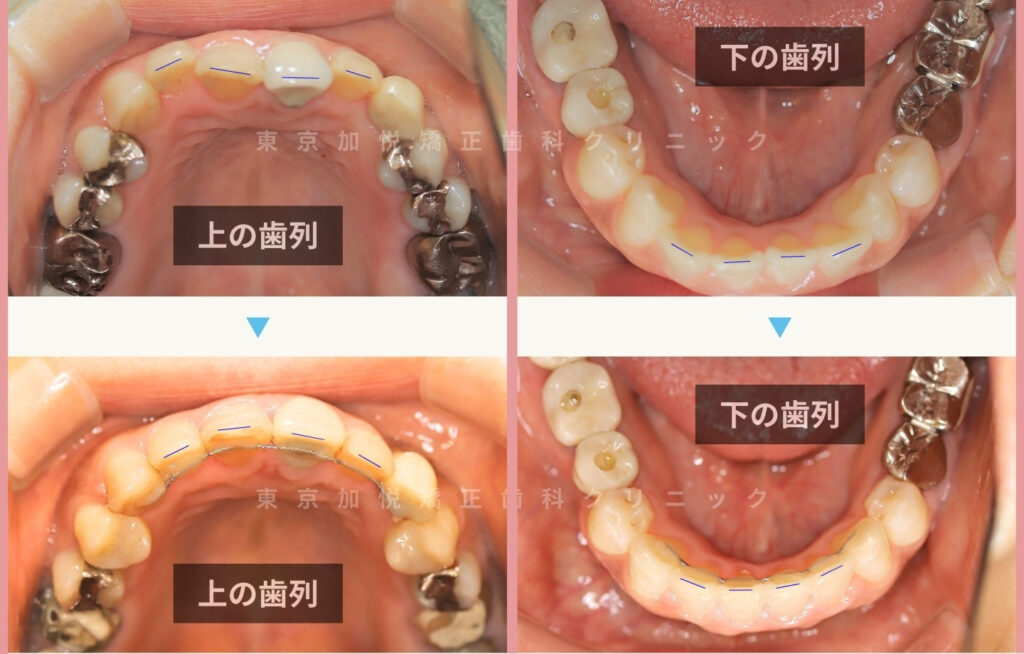

9ヶ月間でクロスバイトが改善されました

患者様のご希望で、治療プラン1の裏側矯正で治療を行いました。

上下前歯だけの部分矯正でもここまで歯列を整えることが可能です。

上の前歯の位置を正しいポジションに移動させることで、反対咬合が改善され、前歯と歯肉のライン(上の写真の青線箇所)のバランスが整いました。

▼咬合面からみた治療前後写真。上下の歯列が綺麗なU字形に整いました。